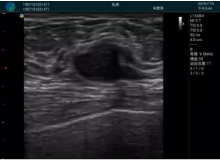

清晰顯示腺體內(nèi)低回聲快影,邊界清晰,包膜較光滑

確定進(jìn)針路徑并實(shí)時(shí)監(jiān)測抽吸針與腫塊位置關(guān)系

抽吸針進(jìn)入腫塊內(nèi)部進(jìn)行旋切

抽吸過程中可見腫塊明顯縮小,并根據(jù)腫塊位置改變針道位置

抽吸旋切后再進(jìn)行超聲復(fù)查,原腫塊區(qū)域未見殘留組織及出血